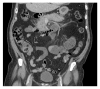

Medications account for a small portion of the various etiologies of acute pancreatitis. Prompt identification of drugs as the inciting factor decreases disease recurrence and unnecessary invasive diagnostic intervention. This case is a report of fenofibrate-induced acute pancreatitis including a disease recurrence with continuation of fenofibrate which subsequently resolved after drug discontinuation. The patient underwent invasive diagnostic evaluation including endoscopic ultrasound with fine needle aspiration and endoscopic retrograde cholangiopancreatography (ERCP). Based on exclusion of other disease etiologies and a positive drug rechallenge, fenofibrate fits as a class 1A medication in the classification of drug-induced pancreatitis.